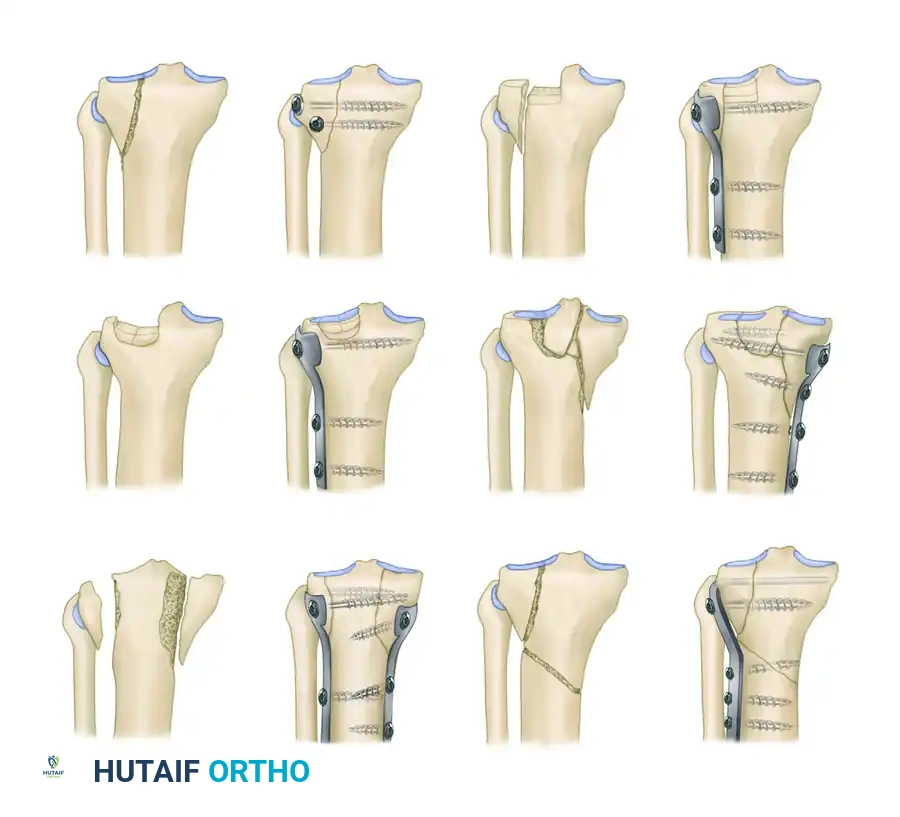

Surgical Diagram of the Schatzker Classification (Types I through VI).

Type I: Pure Cleavage

A typical wedge-shaped, uncomminuted fragment is split off and displaced laterally and downward.

* Pathoanatomy: This fracture is common in younger patients without osteoporotic bone. The dense cancellous bone resists depression, resulting in a pure split.

* Treatment: If displaced, it can be fixed with two transverse cancellous lag screws. If the fragment is large or highly unstable, a small antiglide or buttress plate is recommended to prevent shear displacement.

Type II: Cleavage Combined with Depression

A lateral wedge is split off, but in addition, the articular surface is depressed into the metaphyseal cancellous bone.

* Pathoanatomy: This is the most common tibial plateau fracture, typically seen in patients in their fourth decade or older with early osteoporotic changes. The lateral femoral condyle acts as a hammer, driving the articular cartilage into the metaphysis.

* Treatment: Requires elevation of the depressed articular segment, bone grafting (autograft, allograft, or synthetic bone void filler) of the resulting metaphyseal defect, and stabilization with a lateral buttress plate and subchondral raft screws.

Type III: Pure Central Depression

The articular surface is depressed into the intact lateral metaphyseal rim.

* Pathoanatomy: Occurs almost exclusively in older individuals with severe osteoporosis. The lateral rim remains intact, but the central articular cartilage is crushed downward.

* Treatment: If the depression is significant (typically >5 mm) or causes mechanical axis deviation, it requires a cortical window for elevation, bone grafting, and raft screw fixation.

Type IV: Medial Plateau Fracture

A fracture of the medial tibial condyle, which may be a split or a comminuted depression.

* Pathoanatomy: This is a high-energy injury resulting from varus and axial compression. Because the medial plateau is denser and stronger than the lateral plateau, it requires significant force to fracture.

* Surgical Warning: Type IV fractures carry a high association with popliteal artery injuries, peroneal nerve damage, and severe ligamentous disruption (knee dislocation equivalent).

* Treatment: Requires a posteromedial approach and rigid buttress plating.

Type V: Bicondylar Fracture

Fracture of both the medial and lateral tibial condyles, often with an inverted "Y" pattern leaving the tibial eminence separated from the diaphysis.

* Pathoanatomy: High-energy axial loading. Both condyles are fractured, but the metaphysis remains in continuity with the diaphysis.

* Treatment: Requires dual plating (medial and lateral) or a combination of lateral plating and a medial external fixator to restore the mechanical axis and joint congruity.

Type VI: Plateau Fracture with Metaphyseal-Diaphyseal Dissociation

A transverse or oblique fracture of the proximal tibia is present in addition to a fracture of one or both tibial condyles and articular surfaces.

* Pathoanatomy: The most severe high-energy injury. The dissociation of the diaphysis and metaphysis makes this fracture highly unstable and entirely unsuitable for treatment in traction.

* Treatment: Most should be treated with robust buttress plates and cancellous screws, one on either side if both condyles are fractured. Pin and wire circular fixators (e.g., Ilizarov or Taylor Spatial Frame) have also been strongly advocated for the fixation of these difficult fractures, particularly when the soft tissue envelope precludes extensive dual incisions.